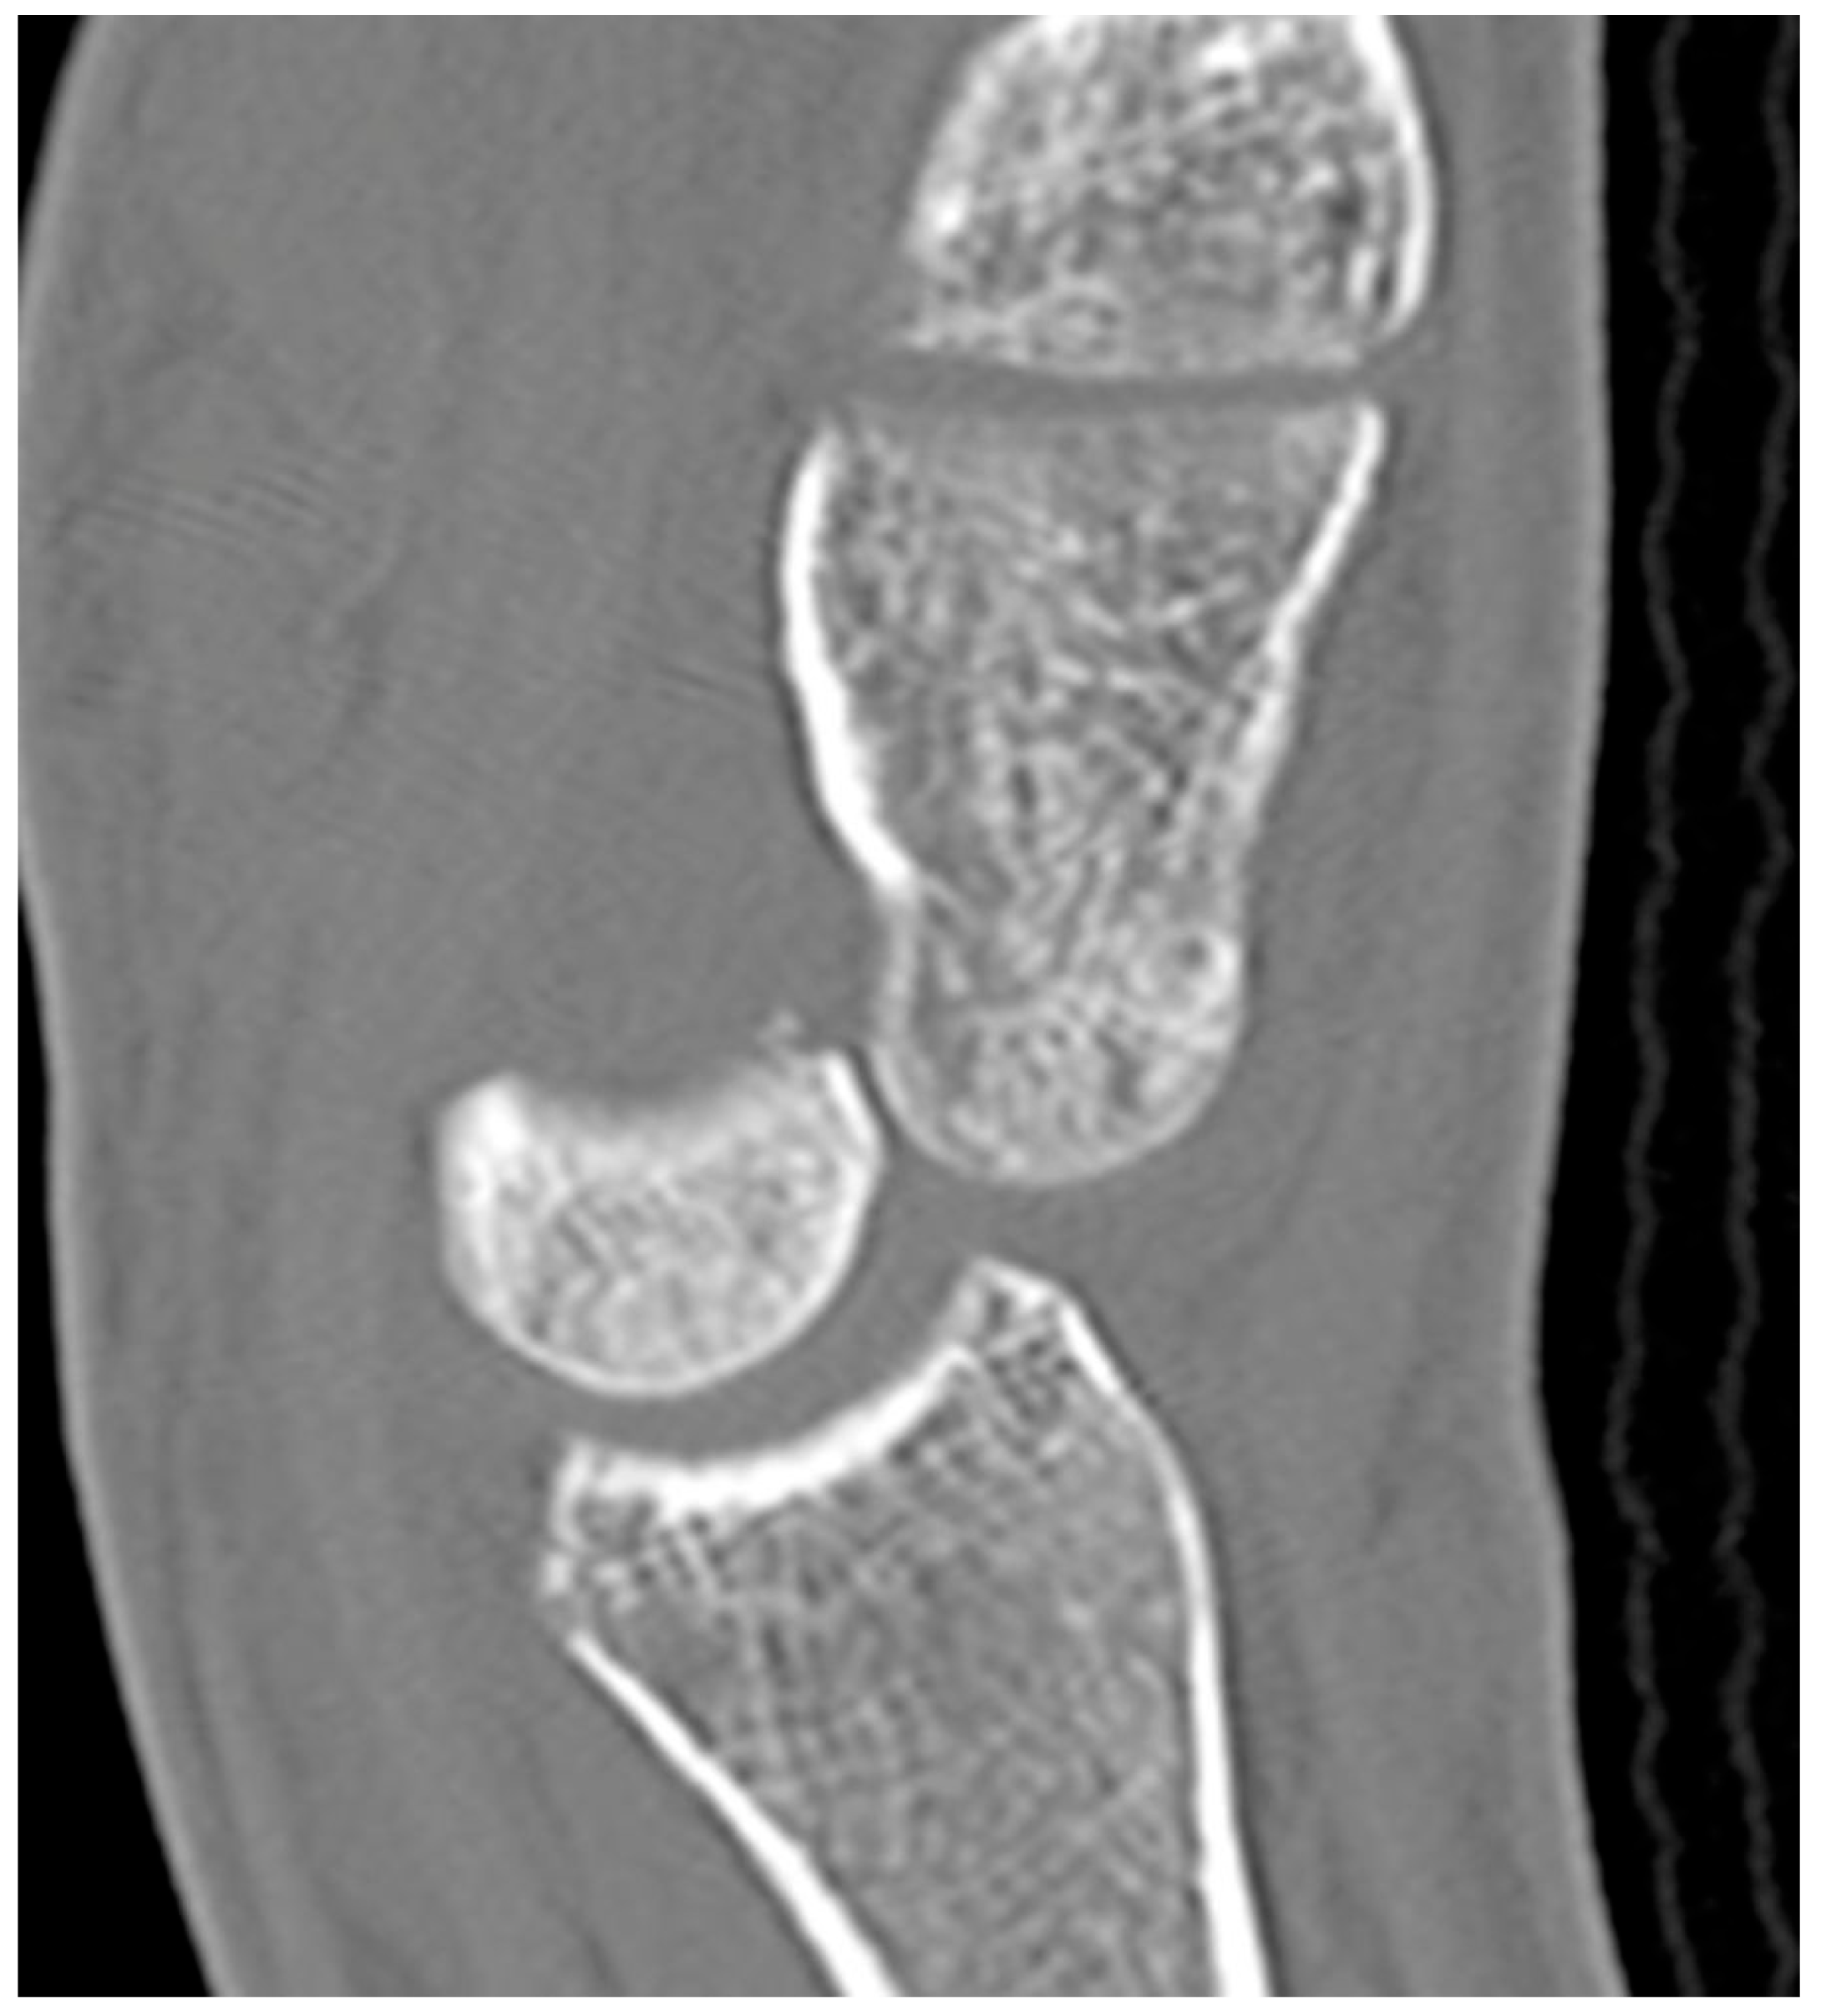

Figure 16. Sagittal reformatted CT of the wrist showing transarticular lunate fracture (arrow).

Lunate fractures are categorized as volar pole, dorsal pole, transverse, osteochondral, and transarticular (Figure 16). Volar pole lunate fractures are the most common and are due to the axial compression from the capitate with the wrist in dorsiflexion and ulnar deviation and additionally may lead to volar intercalated segment instability (VISI) [23]. Like the scaphoid and capitate, the proximal lunate is susceptible to vascular compromise in trauma, with up to 20% of people having only a single palmar nutrient artery supplying the entire lunate. Management of stable, nondisplaced lunate fractures consists of 4–6 weeks of immobilization. Surgical management is indicated for displaced fractures and those with concomitant scapholunate ligament or lunotriquetral ligament injury to preserve the existing anatomy and ensure stability. Chronic fractures with advanced arthritis may even call for partial fusion or proximal row carpectomy [10].